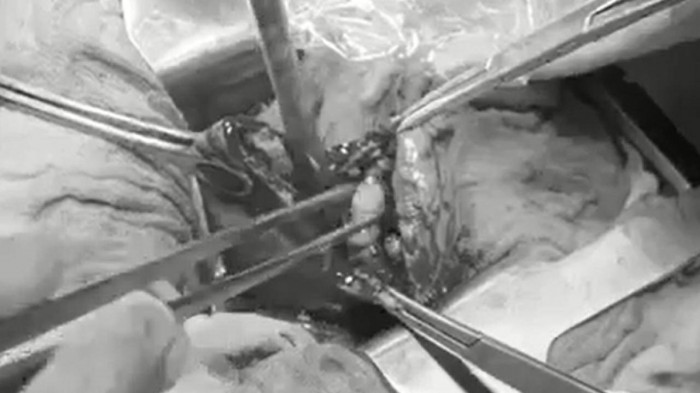

Bác sĩ phẫu thuật gắp sỏi mật cho bệnh nhân

Trực tiếp phẫu thuật cho bệnh nhân, BS. Thưởng cho biết: “Phẫu thuật cắt túi mật có thể được tiến hành bằng phương pháp mổ nội soi hoặc mổ mở. Ở bệnh nhân này ban đầu chúng tôi chọn phẫu thuật nội soi cắt túi mật, nhưng sau đó phải chuyển sang mổ mở do túi mật viêm căng to, tổ chức xung quanh dính nhiều, có rất nhiều sỏi. Mở túi mật của bệnh nhân chúng tôi đã gắp ra 54 viên sỏi, viên sỏi lớn kích thước 27mm”.